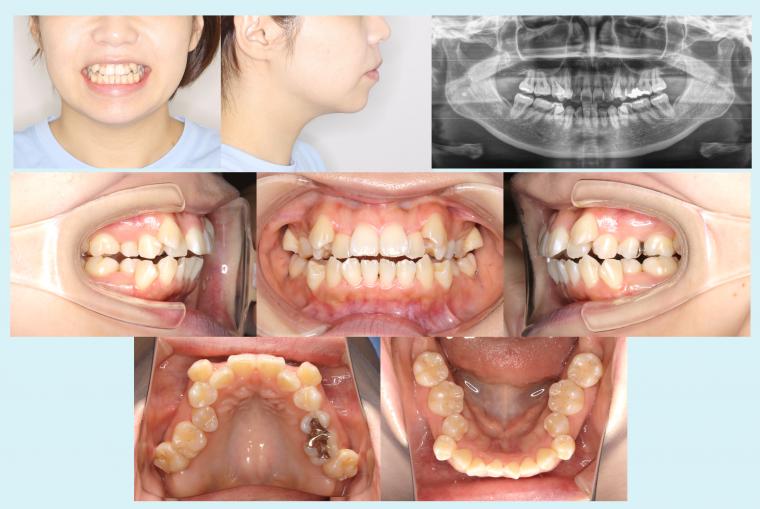

症例集の掲載をスタートいたしました。 - 2022.12.12